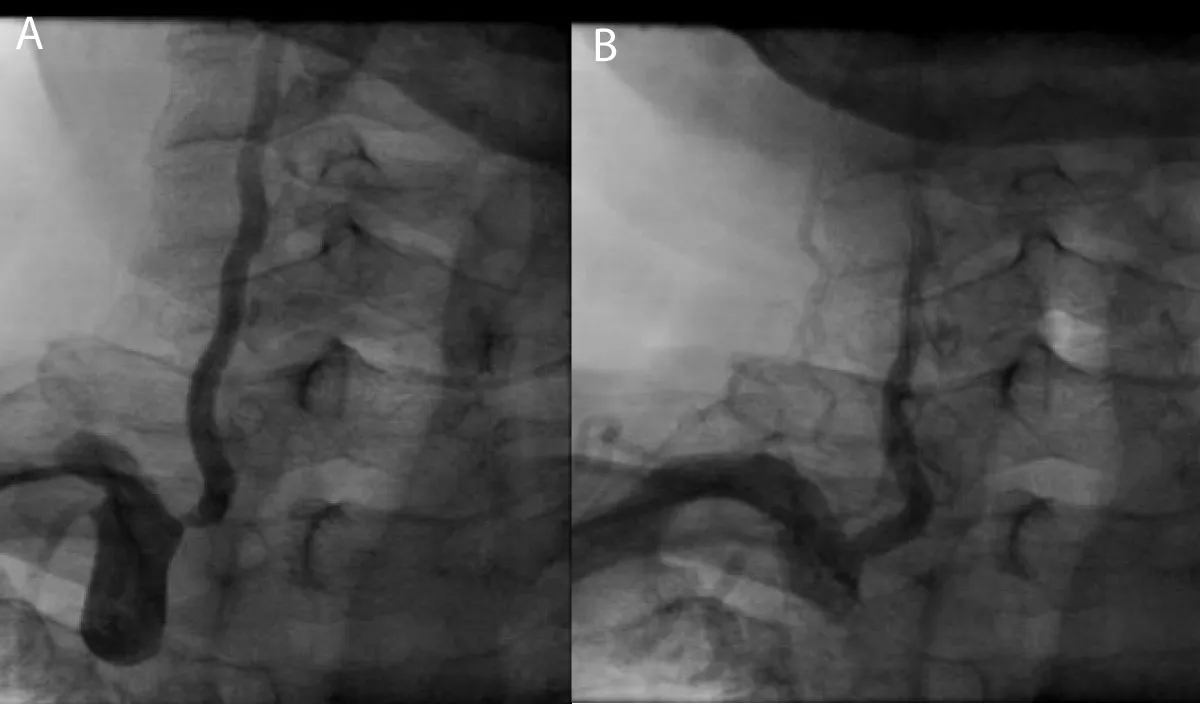

A 63-year-old male patient, previously healthy, hypertensive, diabetic and heavy smoker presented with acute burning chest pain radiating to both shoulders, which was associated with sweating and vomiting for 1 hour, but during hospitalization in the emergency room, he developed sudden onset of altered level of consciousness, dysarthria, nystagmus with National Institute of Health Scale Score (NIHS) score 12, after discussing the case we planned to do coronary and cerebral angiography. On examination the patient looks in pain, sweaty and tachypneic, and their blood pressure: was 75/40 mmHg, Electrocardiography was done and it revealed ST segment elevation in the anterior leads with ST-segment depression in I, II, AVF after that he received 300 mg of aspirin, 300 mg clopidogrel and norepinephrine 3 mcg/kg/min intravenous was started and urgently he was transferred to cardiac catheterization department for primary Percutaneous Coronary Intervention (PCI). During coronary angiography, it showed total occlusion of the proximal left anterior descending artery, stenting was done successfully by using resolute integrity 2.75 x 22 mm drug-eluting stent (Figure 2), then cerebral angiography showed normal anterior and middle cerebral circulation, but there was severe right vertebral artery stenosis, so angioplasty to vertebral artery was planned and it was done successfully (Figure 3), echocardiography was done and it showed reduced left ventricular Ejection Fraction about 30% - 35%, but no left ventricular thrombus was detected, then the patient was followed for 3 days at the hospital and he was discharged on Dual antiplatelet and he had mRS (0) with regular follow up at the outpatient clinic for 3 months, he had the good general condition and functioning well without any neurological deficit mRS (0).

Figure 2: A-coronary angiography shows proximal LAD total occlusion, B-after stent implantation in ostial LAD.

Figure 3: A- Cerebral angiography shows severe right vertebral artery stenosis, B- After successful angioplasty for vertebral artery.